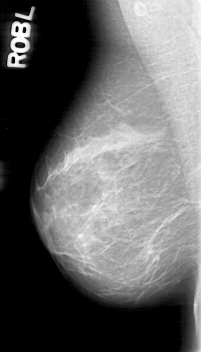

D_4080_1.RIGHT_MLO

RIGHT_MLO LINES 5266 PIXELS_PER_LINE 3001 BITS_PER_PIXEL 12 RESOLUTION 43.5 NON_OVERLAY